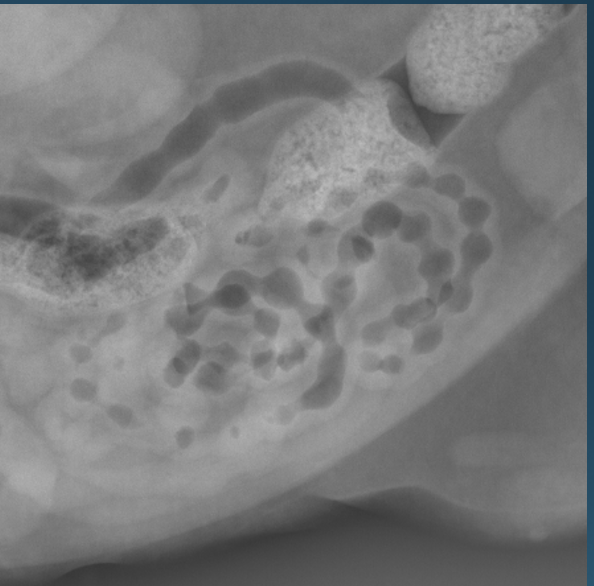

What is shown in this image?

A

“string of pearls” small intestinal appearance in cats